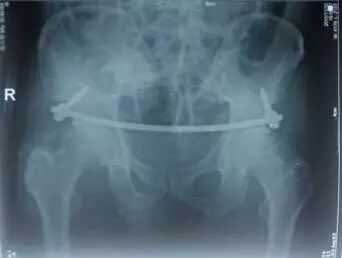

经过检查,医生马三辉诊断吴女士为骨盆多发骨折。骨折部位竟然多达5处,骨盆前、后环都有骨折,骨盆环的稳定性受到严重破坏。

经科室会诊,科主任赵树勇、马三辉等医务人员决定为吴女士实施骨盆骨折闭合复位内固定微创手术。

术中,马医生在吴女士下腹部切了3个横行小切口,将固定长棒折弯至合适弧度后,通过两侧对称切口穿入,固定在预先拧入的髂棘上椎弓根螺钉内,恢复了骨盆环的稳定性。